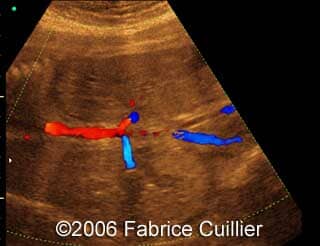

- Bilateral kidney’s enlargement without increased echogenicity. The corticomedullary differentiation seemed normal

Kidney"s enlargement